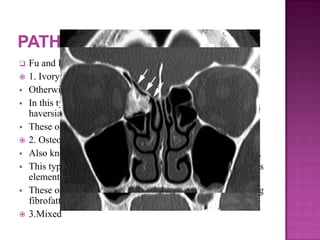

 Fu and Perzin classification:

 1. Ivory / compact osteoma:

 Otherwise also known as eburnated osteoma.

 In this type of osteoma the bone is very dense and lacks

haversian canals.

 These osteomas develop from membranous elements.

 2. Osteoma spongiosum:

 Also known as mature osteoma is composed of softer bone.

 This type of osteomas are known to arise from cartilaginous

elements.

 These osteomas have little medullary component containing

fibrofatty tissue.

 3.Mixed